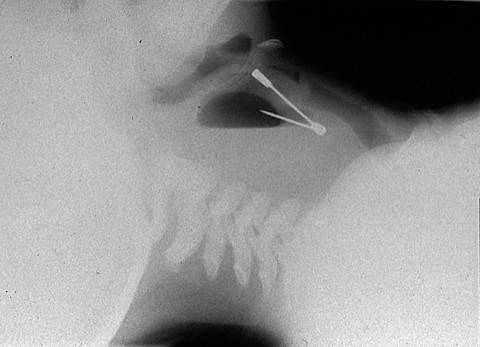

Stick a needle in my neck I can't breathe